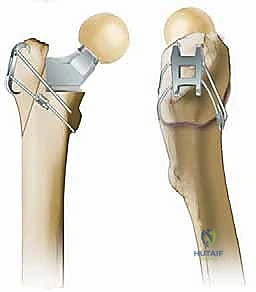

* التصميم المخروطي (Tapered Design): الساق تأخذ شكلاً مخروطياً يضيق تدريجياً نحو الأسفل. هذا التصميم يسمح للساق بالانحشار بقوة داخل القناة النخاعية لعظم الفخذ، مما يوفر استقراراً محورياً (Axial Stability) يمنع الساق من الغوص لأسفل تحت تأثير وزن المريض.

* الأخاديد الطولية (Flutes): يحتوي سطح الساق على أخاديد أو شقوق طولية بارزة. عندما يتم إدخال الساق في العظم، تنغرس هذه الأخاديد في القشرة العظمية الداخلية، مما يوفر استقراراً دورانياً (Rotational Stability) ممتازاً، ويمنع الساق من الالتفاف داخل العظم.

2. السيقان المعيارية مقابل الأحادية (Modular vs. Monoblock Stems)

في الممارسات الحديثة، يفضل الدكتور هطيف غالباً استخدام السيقان المعيارية (Modular Stems). هذه السيقان تتكون من جزئين منفصلين (جزء سفلي ينغرس في العظم، وجزء علوي يتصل بالرأس المفصلي).

* ميزة السيقان المعيارية: تتيح للجراح تثبيت الجزء السفلي بقوة في العظم أولاً، ثم اختيار الجزء العلوي المناسب بدقة متناهية لضبط طول الساق (Leg Length) وزاوية الانحراف (Offset)، مما يضمن استعادة الميكانيكا الحيوية المثالية لمشية المريض وتقليل خطر الخلع.